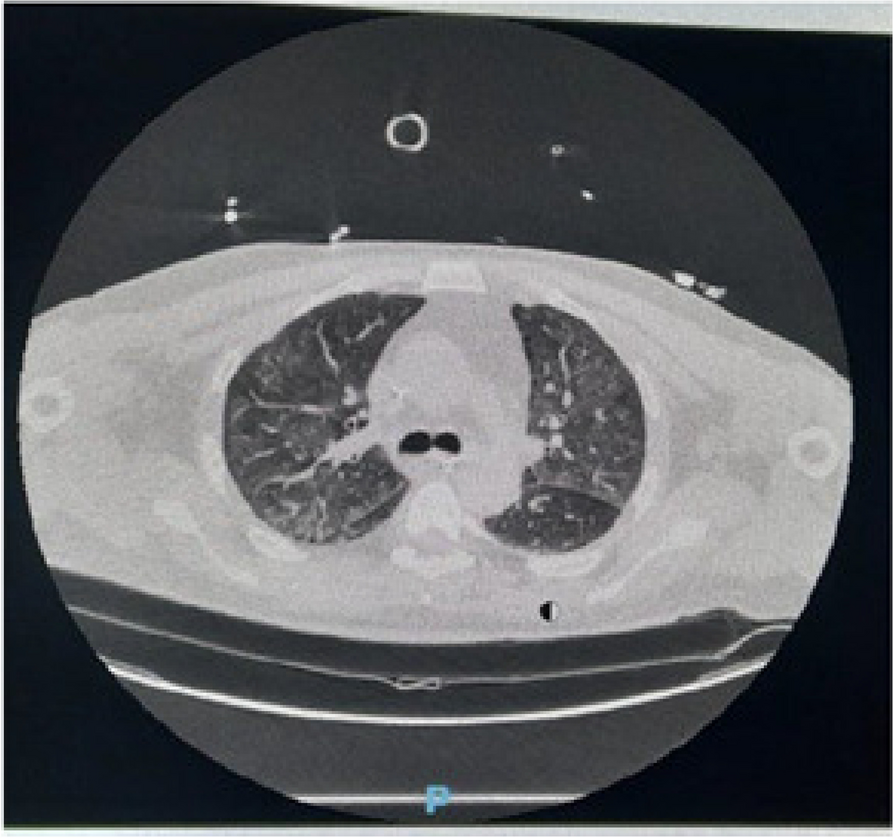

A few hours after the admission in ICU he reported a blunt abdominal pain, mainly on the right side, nausea and the exams showed increased amylase levels, urologists excluded any surgical involvement of pancreatic tissue and suspected a transient sphincter of Oddi dysfunction [3]. After one night in ICU he was transferred to the urology ward due to his clinical stability, even though Amylase peaked at 2340 U/l. Two days later abdominal pain increased to severe, with characteristics of peritonism and increased inflammatory markers. An abdomen-thorax CT scan revealed acute pancreatitis (AP) (Figure 1) and he was transferred to ICU. He started a standard treatment for acute pancreatitis and antibiotic therapy [4].

In fact, Propofol is listed as a possible cause of AP, class Ib, based on the classification of Badalov et al. [7]. Following the scheme proposed by the systematic review by Haffar et al for Propofol induced AP [6] we could confirm that our hypothesis is plausible. He satisfied the American College of Gastroenterology criteria for AP [8,9] and it is classified as severe acute pancreatitis according to the Revised Atlanta Classification with peripancreatic necrotic fluid collection [10]. Marshall score [11] after admission was two and Naranjo et al [12] probability scale for drug adverse reaction was three, meaning that the adverse reaction is possible. Latence according to Badalov et al [7] has been short or intermediate. Exclusion of other plausible causes, timing of pancreatitis symptoms and previous cases in literature support our hypothesis of propofol induced pancreatitis.

Fig. 1 (abstract A21).

See text for description